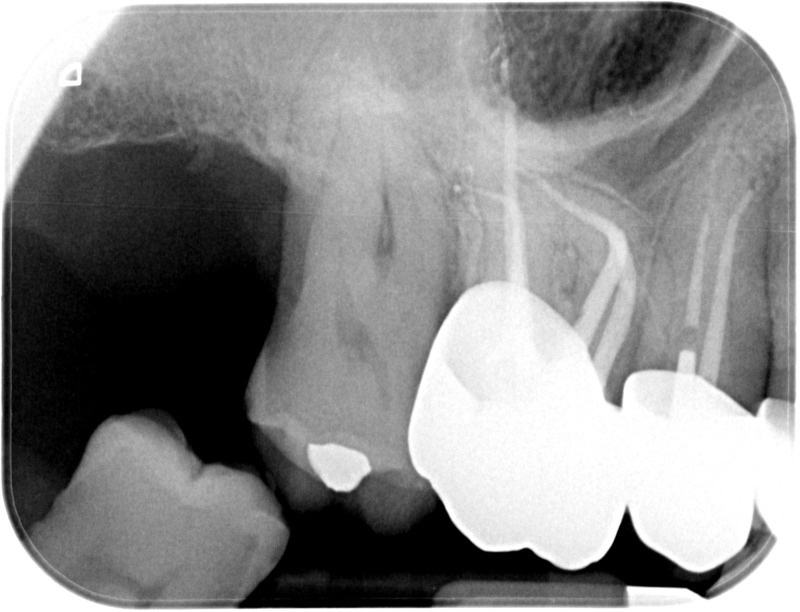

• Traitement endodontique : Sous anesthésie locale et à travers la protection d’un champ opératoire nous accédons à la pulpe de la dent à soigner, puis aux canaux de ses racines que nous devons désinfecter. Ce soin nécessite l’élimination complète de la source de contamination (souvent la carie) parfois sous une ancienne reconstitution ou une couronne qu’il faut alors retirer. Une fois le nettoyage et la mise en forme des canaux réalisés, nous les obturons de façon hermétique avec un ciment et un matériau thermoplastique appelé Gutta Percha. Ceci afin d’empêcher une nouvelle prolifération bactérienne et d’assurer le maintien de la dent dans ses structures de soutien (ligament parodontal et os alvéolaire). L’ouverture effectuée au centre de la dent sera d’abord refermée avec un pansement provisoire avant d’envisager ensemble la reconstitution d’usage : un composite, un inlay-onlay ou une couronne.

Avant